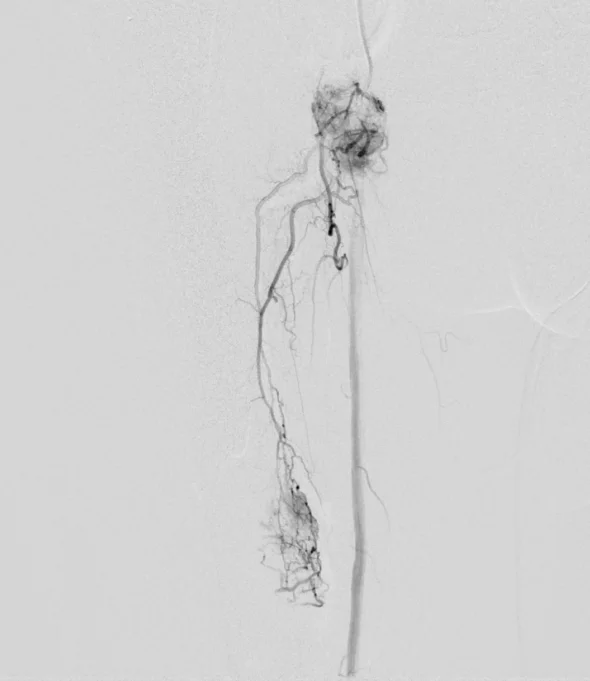

Preoperative Embolization: Case 1

72 year old patient with renal cell CA metastatic to bone presents for preoperative embolization prior to surgery.